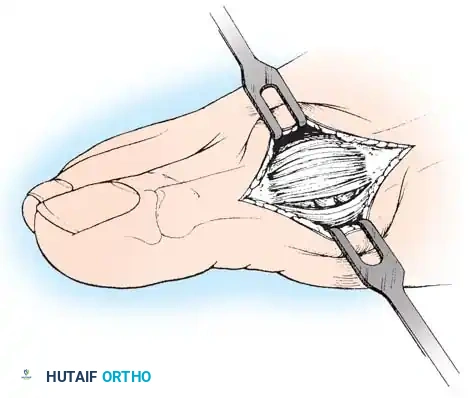

• If after complete adductor hallucis release and preferably after a lateral capsular release, a fi bular sesamoidectomy is needed to correct the valgus deformity of the great toe fully, it should be done at this time.

• Adequately separate the fi rst and second metatarsal heads for exposure.

• Plantar fl ex the metatarsophalangeal joint 10 to 20 degrees, which reduces tension on the sesamoids.

• Grasp the fi bular sesamoid with a small Kocher clamp or sturdy tissue forceps, and pull it laterally into the intermetatarsal space (Fig. 78-20).

• Release the intersesamoid ligament. When this ligament has been incised, bring the fi bular sesamoid into the intermetatarsal space, where its removal is straightforward. Care must be taken when incising the intersesamoid ligament to avoid severing the fl exor hallucis longus tendon immediately plantar to it. If the tendon is severed, it probably should not be repaired at this level; loss of the tendon causes little if any functional impairment, and